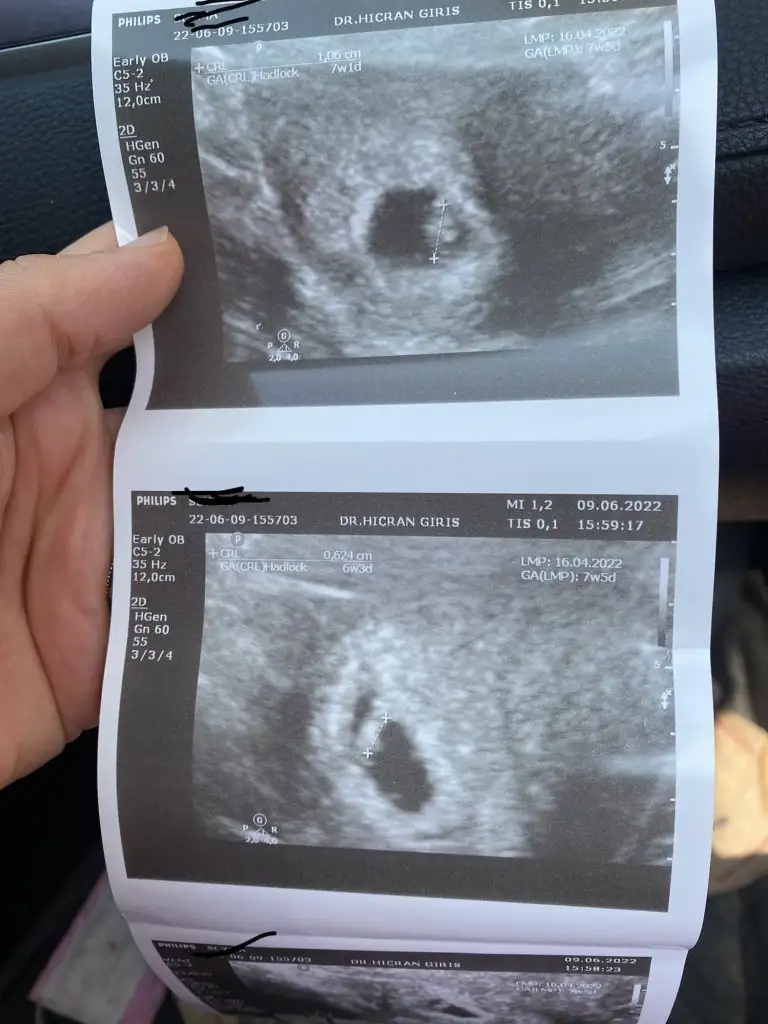

Benim içinde yorum yaparsanız sevinirim vajinal ultrason 6+3

Eklentiler